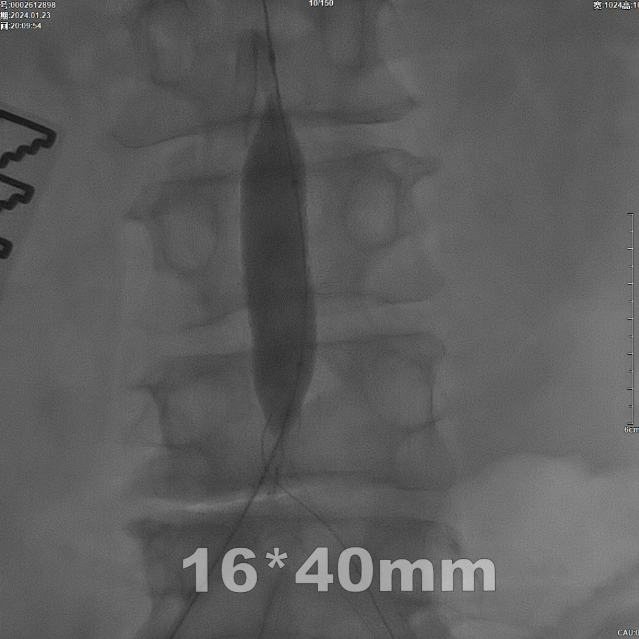

后扩张处理

首先使用14mm球囊进行初步扩张,鉴于腹主动脉直径约15mm,最终选用16mm球囊进行扩张。

当扩张压力达10 ATM时,患者出现轻微疼痛,遂停止扩张。扩张前需将左侧导丝撤出,扩张后重新置入并确认导丝位于支架内。

再用8mm球囊对双侧髂支腹主动脉段行对吻扩张,以确保双侧髂支与腹主动脉覆膜支架腔内获得良好的贴壁形态,最大程度减少空腔,降低远期再狭窄发生率。